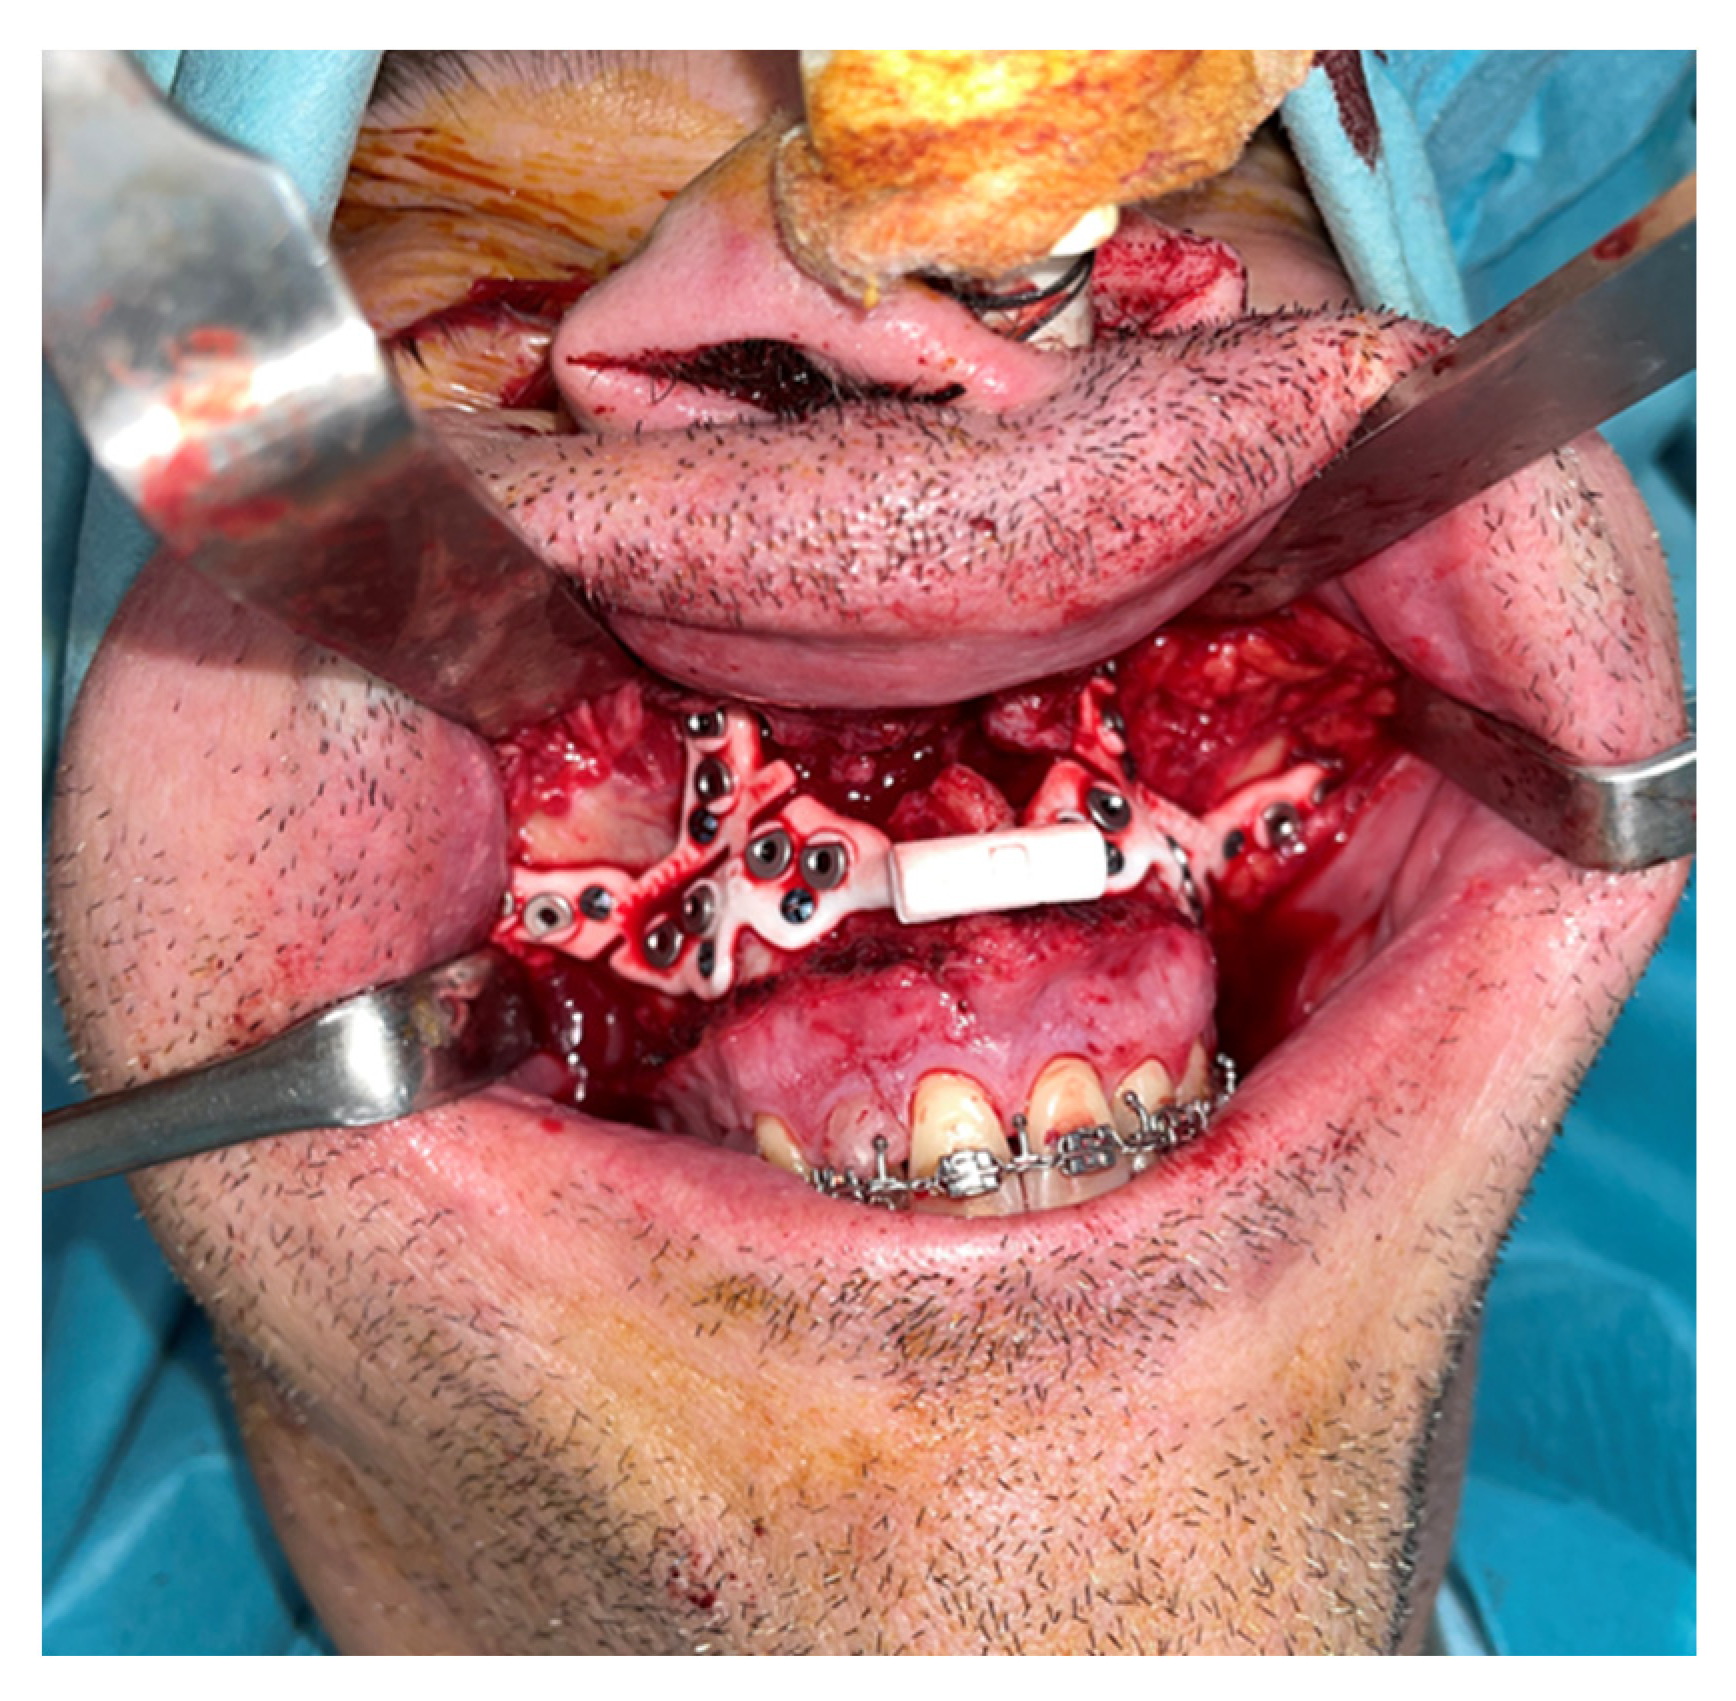

Prior to surgery, helical CT scans were performed with the following parameters: 0.625 mm slice thickness, voxel size of 0.5 × 0.5 × 0.625 mm, 120 kVp, and 200 mA. Head and neck scans were acquired in natural head position with the patient in supine position. These scans, along with occlusal records obtained through digital models and clinical photographs of the patient, were integrated into the Dolphin Imaging surgical planning software version 11.95®. Using these records, a 3D reconstruction of the patient’s skull was created, aligned with its natural head position. The Le Fort and BSSO osteotomies were then designed. The planned movements of the maxilla and mandible were virtually simulated (Figure 1), and an intermediate and final splint were designed for a maxilla-first sequence treatment, which were then 3D printed.

Figure 1. Step 1. The green mandible represents the preoperative mandibular position. The blue mandible ilustrates the postoperative (planned) position of the distal mandibular segment following virtual repositioning The yelow structures correspond to the cranial base and proximal mandibular segments, serving as stable reference points during simulation. The white maxilla and dentition are shown as unchanged anatomical references, used to guide occlusion and evaluate surgical accuracy.